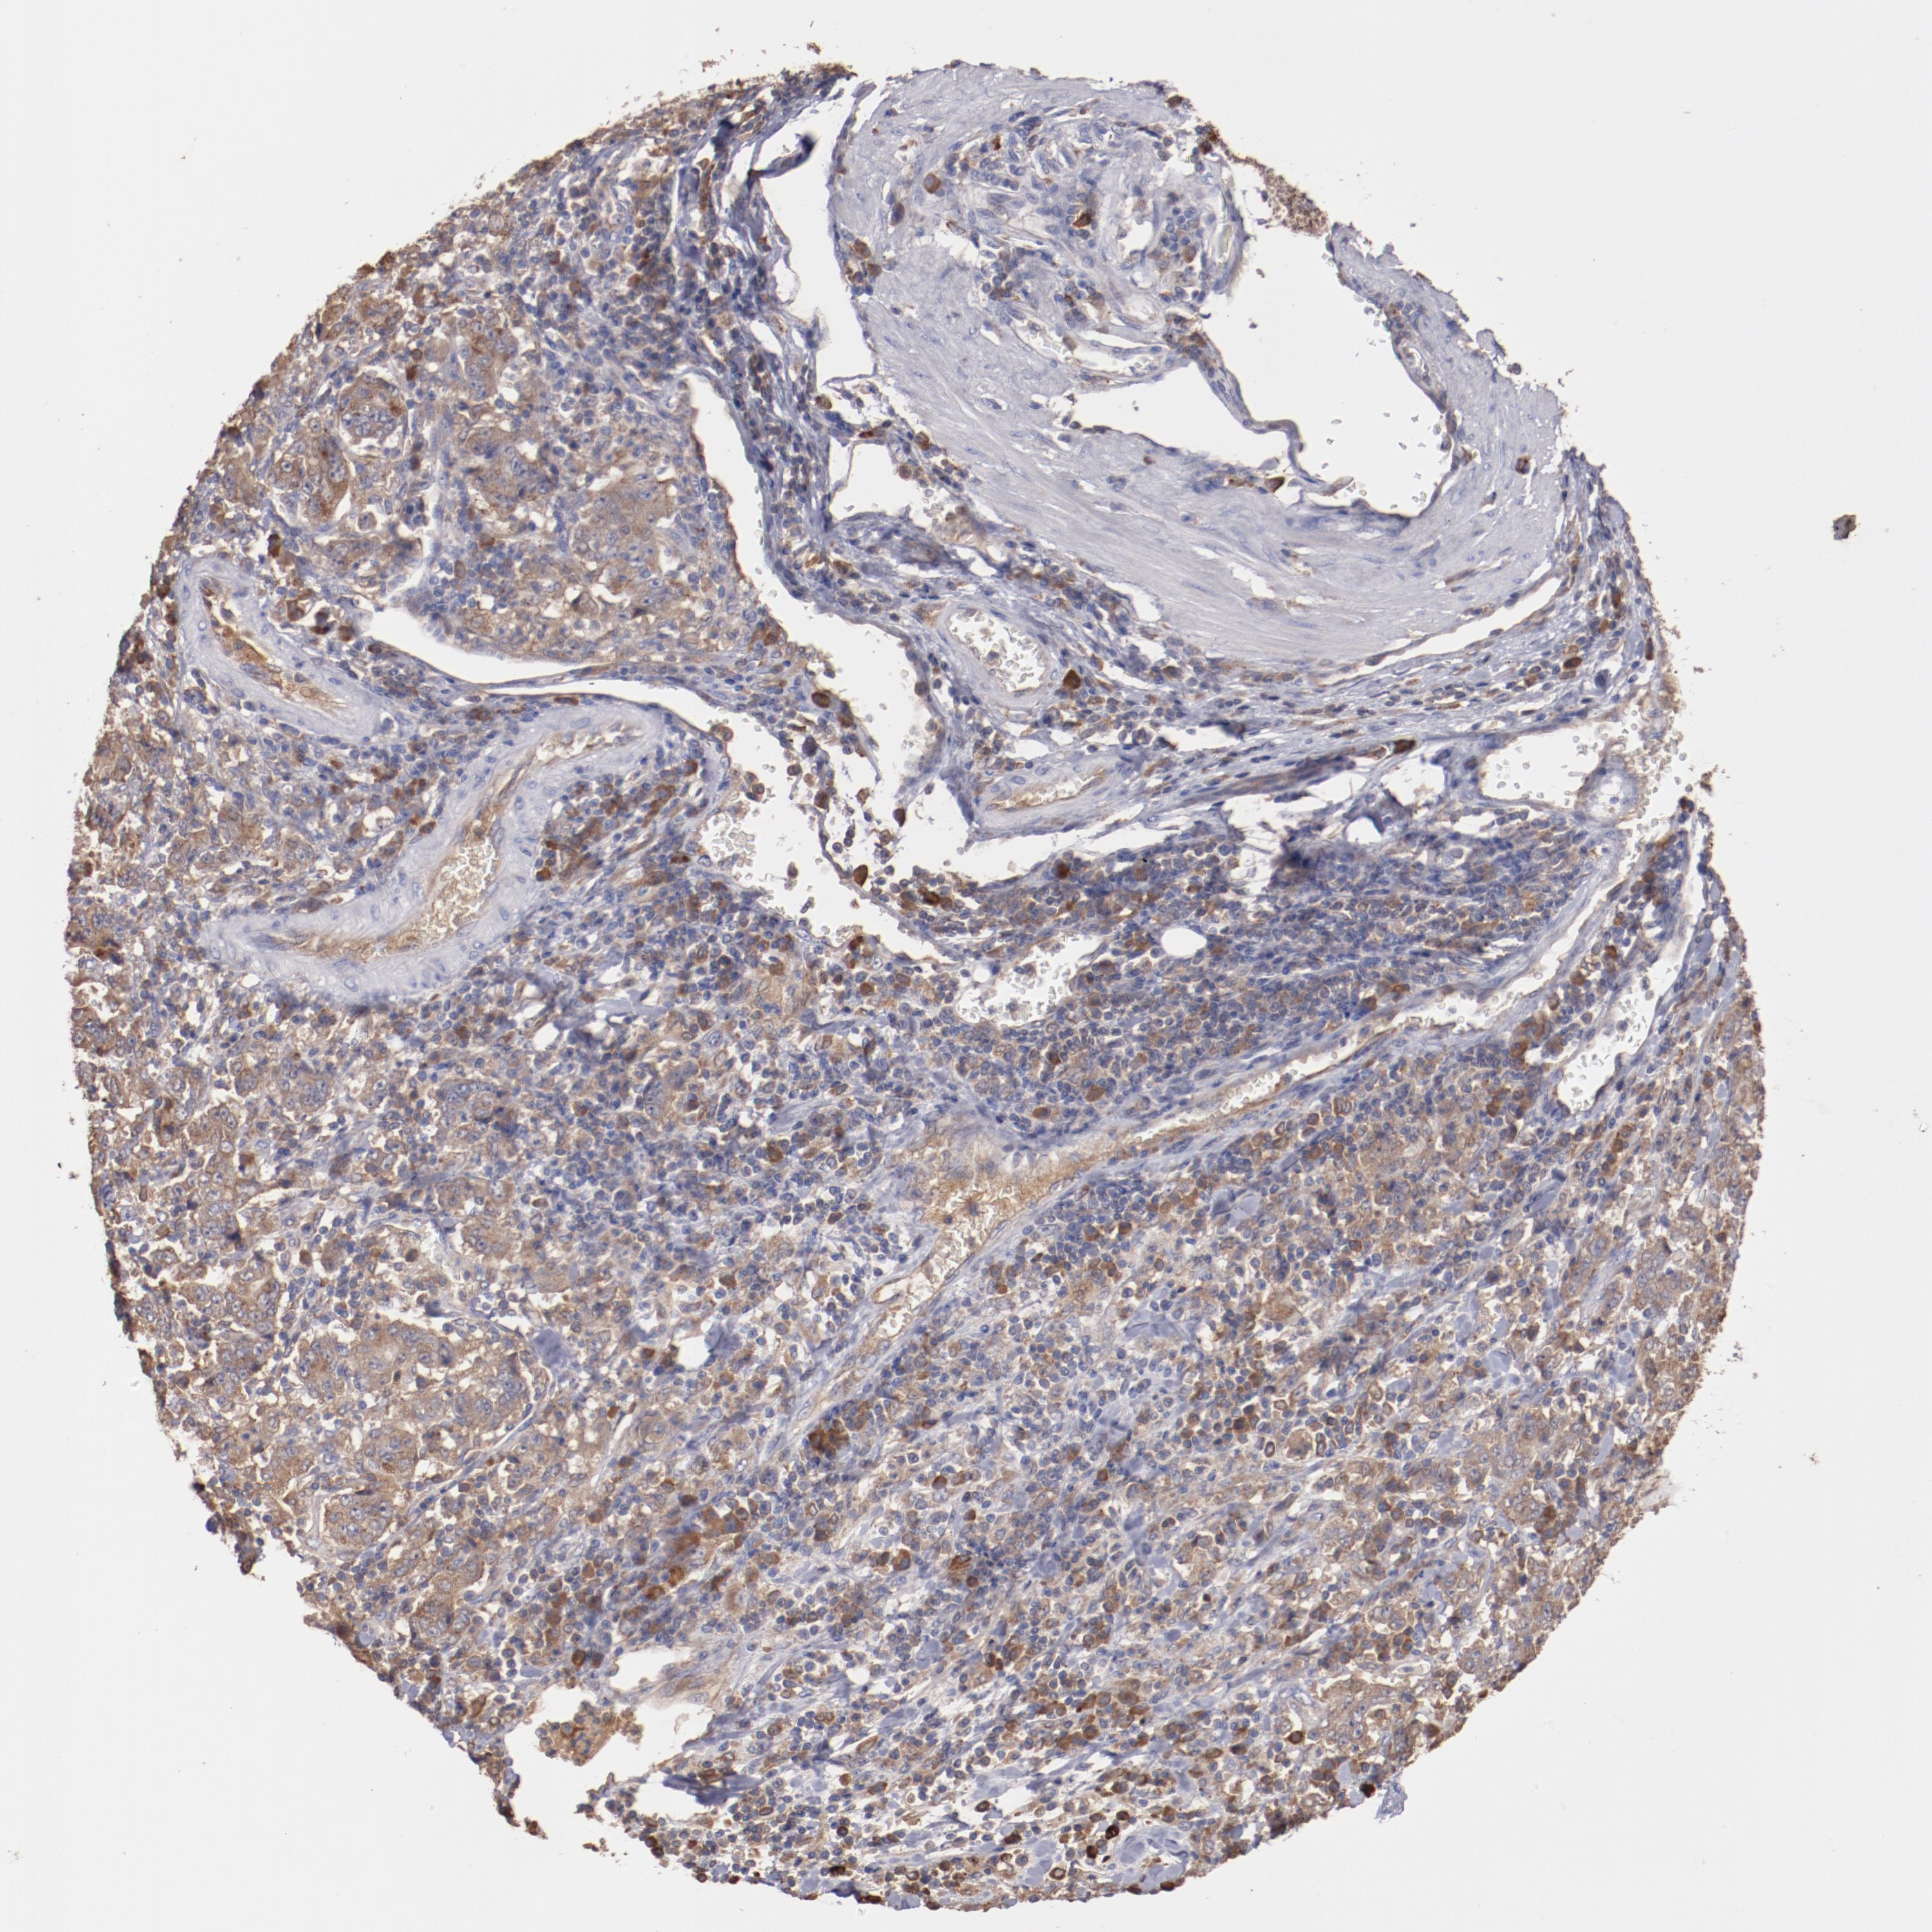

STOMACH CANCER - Protein expressioni

A mouse-over function shows sample information and annotation data. Click on an image to view it in a full screen mode. Samples can be filtered based on level of antibody staining by selecting one or several of the following categories: high, medium, low and not detected. The assay and annotation is described here.

Note that samples used for immunohistochemistry by the Human Protein Atlas do not correspond to samples in the TCGA dataset.

Antibody stainingi

Antibody staining in the annotated cell types in the current human tissue is reported as not detected, low, medium, or high, based on conventional immunohistochemistry profiling in selected tissues. This score is based on the combination of the staining intensity and fraction of stained cells.

Each image is clickable and will lead to virtual microscopy that enables deeper exploration of all samples and also displays staining intensity scores, fraction scores and subcellular localization as well as patient and tissue information for each sample.

Antibody HPA002692

Antibody HPA005941

Antibody CAB010272

Staining

High

Medium

Low

Not detected

Intensity

Strong

Moderate

Weak

Negative

Quantity

>75%

75%-25%

<25%

None

Location

Nuclear

Cytoplasmic/membranous

Cytoplasmic/membranous,nuclear

Adenocarcinoma, NOS

Adenocarcinoma, High grade